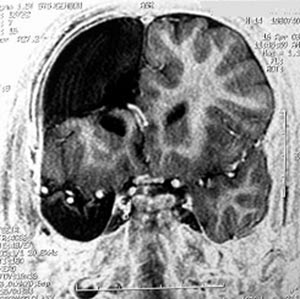

5b) Displasia cortical têmporo-occipital (lobos temporal e occipital)

Figura 69 - Ressonância nuclear magnética pré-operatória.